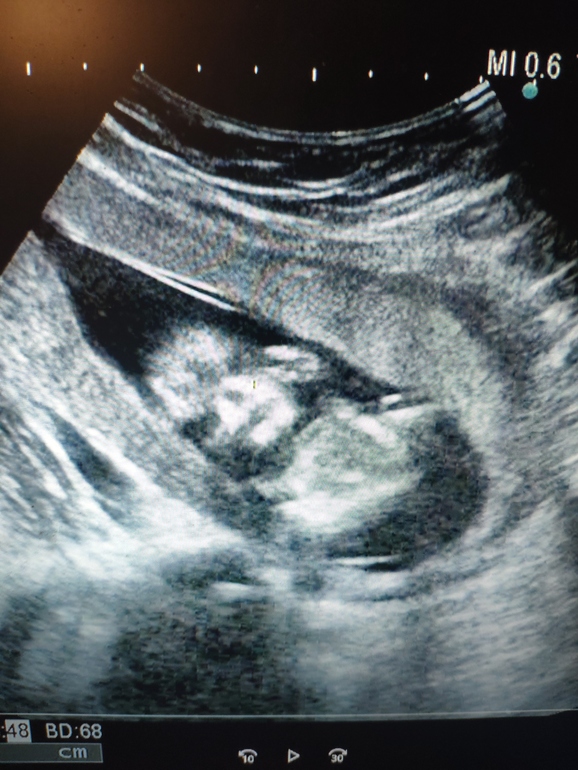

Мечты сбываются !💖 Это девочка 🥰💖 И моя 17я неделька

Как я благодарна вселенной ! Мечтала о двух дочках и сыне и вот УЗИ ...Говорит мальчуковых принадлежностей нет ,показывает наш "гамбургер" ))) Говорит ну вы же понимаете ,это не 100 процентов ... Но я надеюсь что у нашей девочки ничего не отрастет 😆🤭

Теперь о моей крошечке. Которая очень подросла ! Вес 146 г . Плацента по передней стенке, к зеву 28 мм, низковата,но сказали не критично ,поднимется скоро. Все в норме остальное. Чувствую с 16 недели очень отчётливо. Тихоня ,крутится больше , пиночки деликатные ,редко. Вот и она 🥰